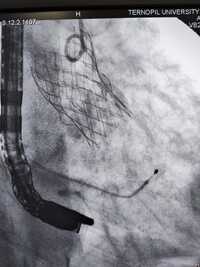

Одна з них має важке викривлення хребта, внаслідок якого анатомічно складне положення серця, аорти та інших внутрішніх органів. Це практично унеможливлювало виконання заміни клапана іншим доступом окрім трансапікального, що, власне, було й проведено.

Суть операції полягає в тому, що на працюючому серці виконується невеликий отвір, на якому через трубку-катетер по провіднику вводиться згорнутий клапан. Позиціонування контролюється як рентгенівським зображенням, так і черезстравохідним ультразвуковим датчиком.

Після імплантації хірург затягує вузол навколо отвору і вшиває рану. Крововтрата є мінімальною. Це новий рівень кардіохірургічних операцій, кажуть медики.

До слова, лікарня вже має досвід імплантації шести аортальних клапанів через стегнову артерію. Тепер ж освоїли і цю методику, яка має свої переваги для певної групи пацієнтів.